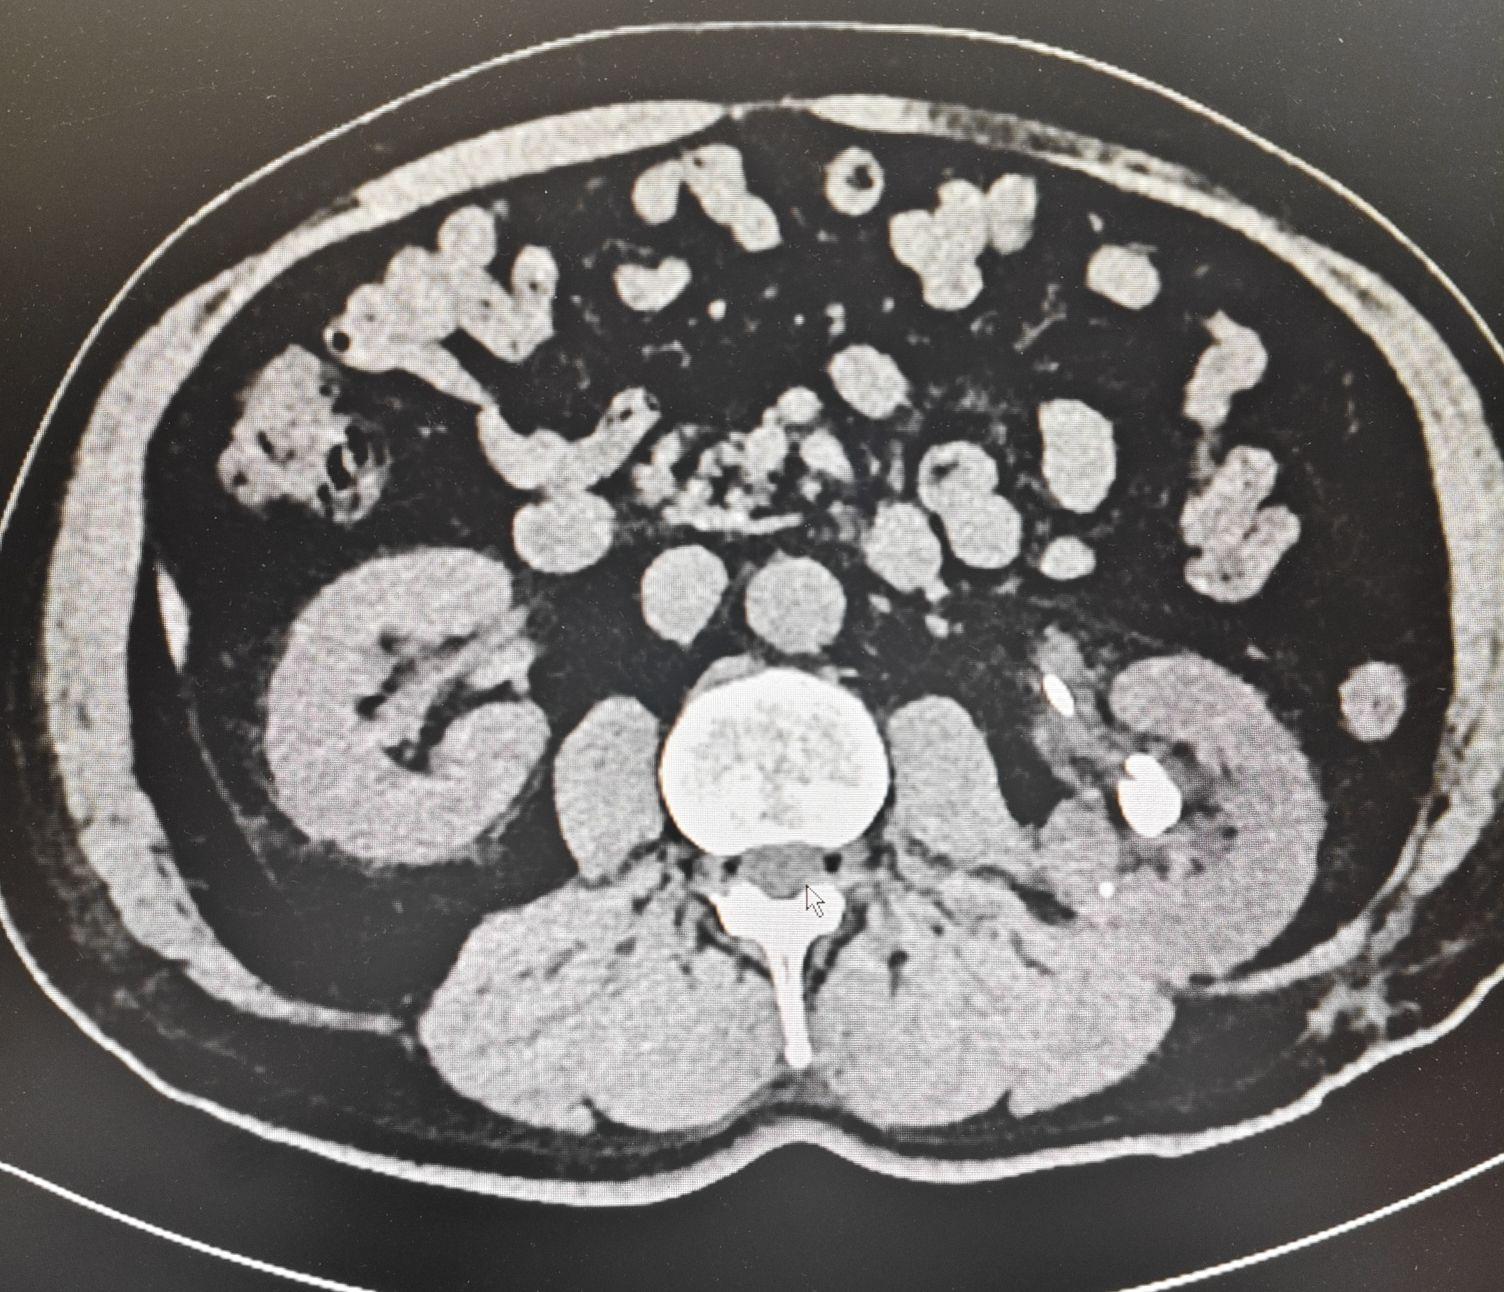

026年1月8日行腹部CT平扫加盆腔CT平扫加薄层,较前2025-12-16下腹部盆腔CT对比,左侧输尿管内双J管置入术后改变,左肾盂输尿管中度扩张积水较前稍减少,左肾密度减低较前好转,左肾周输尿管周围渗出较前稍增多,左肾多发结石,较前原左输尿管上段肾盂移行区结石上移改变,左肾边缘线状高密度影,请结合病史,右肾周渗出较前变化不著,膀胱充盈差,壁增厚,前列腺内钙化灶,较前变化不著,左侧腹股沟疝,较前稍进展,骨盆部分骨质陈旧性骨折畸形愈合,部分骨不连,右坐骨支旁多发小骨片影,骨盆周围部分肌群萎缩,脂肪浸润,较前变化不著,血分析加全程C反应蛋白中性粒细胞百分比75.2%,肾功肝功血糖电解质eGFR(CKD-EPI)80.46,尿液分析白细胞(9-HR)500(3+)cells/μL,隐血(9-HR)7.5(3+)mg/L,尿蛋白(9-HR)0.3(1+)g/L,白细胞(镜检)2-4/HP,十二通道心电图检查窦性心律心电轴左偏大致正常心电图。

患者以左侧输尿管支架管置入术后20天主诉入院,专科情况双肾区无隆起,肾下极未触及,双肾区压痛阴性叩痛阴性,双输尿管走行区压痛阴性,耻骨上区压痛阴性,叩诊鼓音,阴茎发育正常,包皮不长,尿道外口无红肿及异常分泌物,双侧睾丸附睾形态均正常,直肠指诊未查,辅助检查立位腹部平片提示左肾区结石,双J管位置正常,CT提示左肾多发结石,左侧输尿管双J管置入术后改变,尿道狭窄既往有尿道成形修补术史,术中见尿道膜部狭窄呈针眼状,尿液分析提示白细胞及隐血阳性,提示泌尿道感染,同时存在前列腺增生表现。